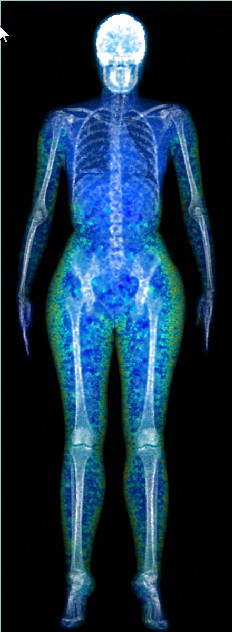

DEXA scans, what is the benefit of getting more than one scan?

All of our clients at Body Measure know that DEXA scans are the gold standard for body composition. The most …

Not happy with your DEXA scan results? It’s not personal

We’ll be upfront. Having a DEXA scan can sometimes be a bit confronting. Knowing EXACTLY how much fat is on …

Get a picture of your bone health

How healthy are your bones? Do you even think about your bones? After all, bones are hidden away, just doing …